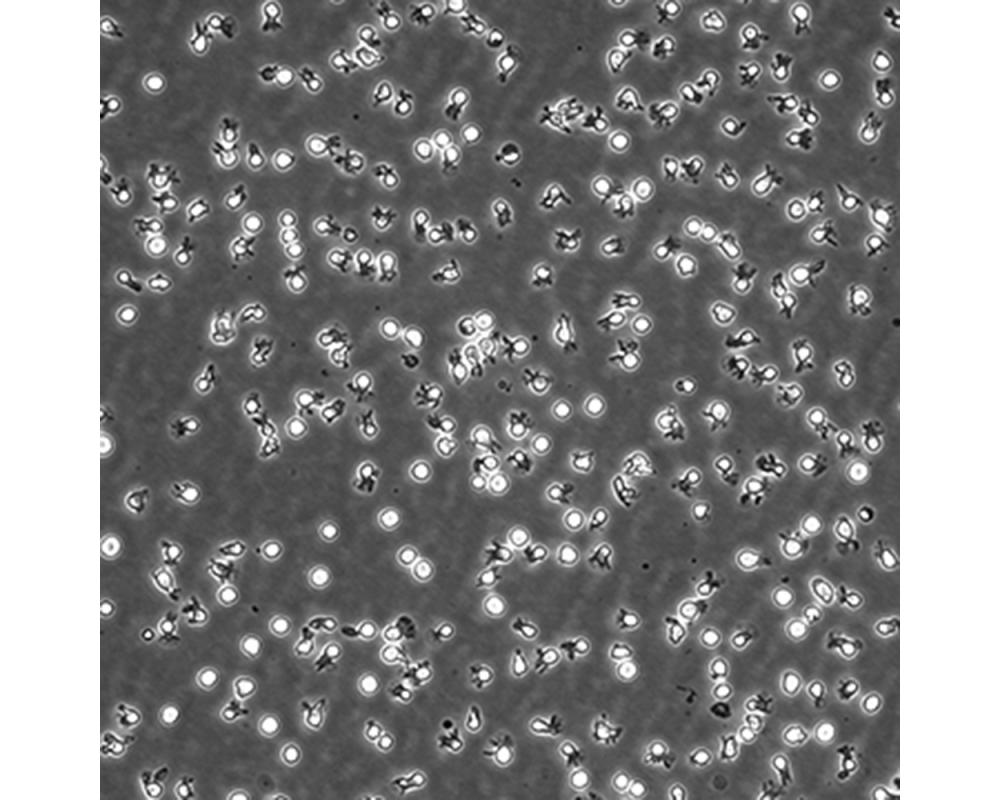

中文名稱 人彌漫大B細(xì)胞淋巴瘤細(xì)胞

組織來源 彌漫大B細(xì)胞淋巴瘤;男性

生長特性 懸浮

培養(yǎng)基 IMDM,90%;FBS,10%;雙抗。

傳代方法 Maintain cultures at a cell concentraion between between 1 X 10(5) and 1 X 10(6) viable cells/ml.

培養(yǎng)條件 Atmosphere: Air, 95%; CO2, 5%。Temperature: 37℃